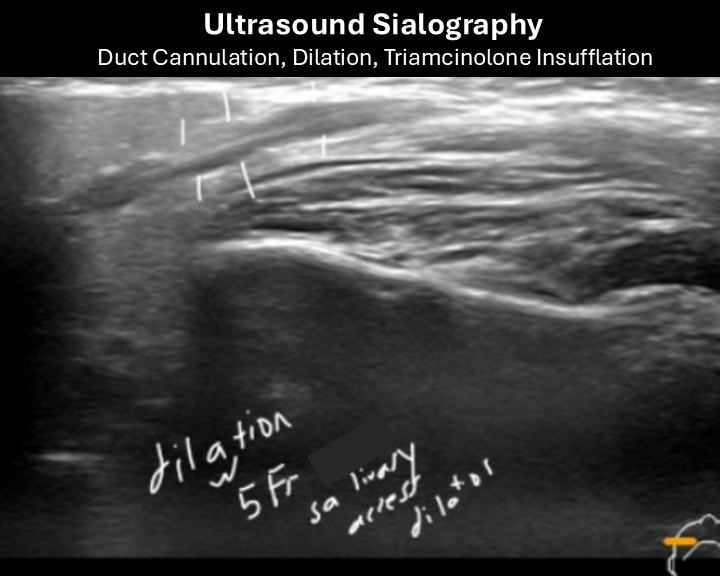

5. 15 months after sialogram

In Clinic Procedure Parotid Duct Dilation (5 Fr Dilator), Cannulation and Kenalog 10 Insufflation "Ultrasound Sialogram"  (see further below)

In-Clinic 15 months after sialogram

Ultrasound Sialography - Parotid Duct Cannulation, Dilation, with Triamcinolone Insufflation

ultrasound sialography 1

ultrasound sialography 2

ultrasound sialography 3